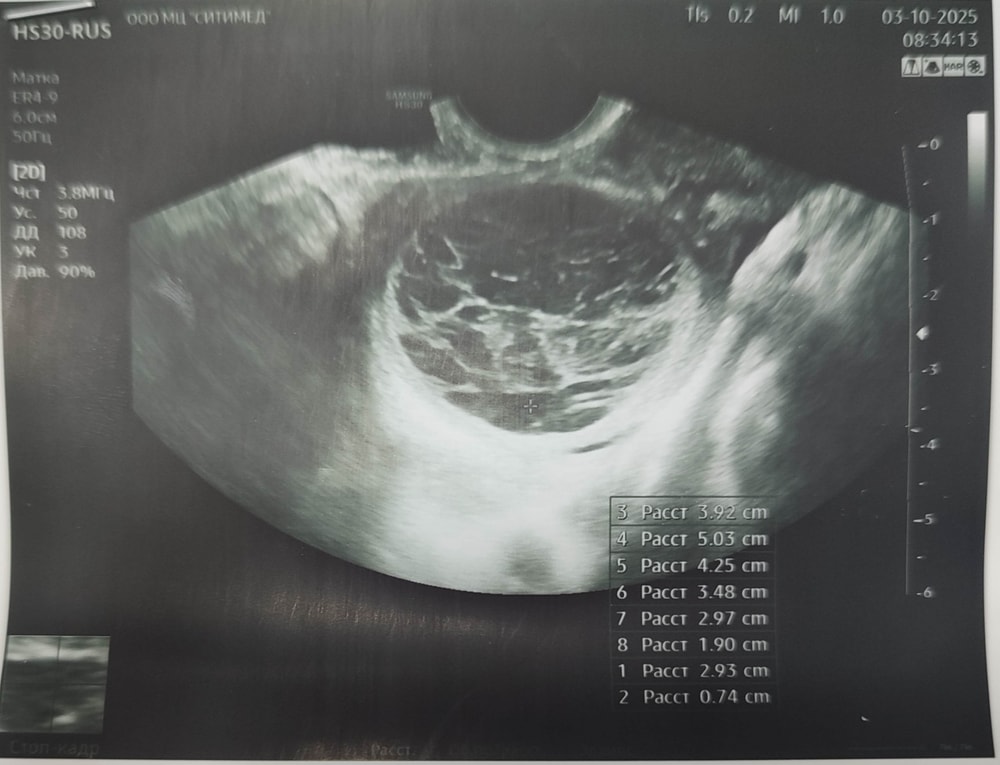

Случайно поймала раннюю овуляцию на 10й дмц. Записалась на УЗИ что бы подтвердить её. За день до этого начал болеть правый яичник, что меня очень-очень обрадовало, ведь он спал у меня почти год после операции и только с той стороны у меня есть труба. Но по мере нарастания боли я поняла что что-то идёт не так...Когда гиня стала диктовать данные с кистой почти 5 см, я очень расстроилась, сказала ей что был пик по тестам 3 дня назад, и я думала что сегодня подтвердим О. И она говорит " Так может у вас и была овуляция, это же киста ЖТ"🫤

Но в заключении этого не написалаМожно ли вообще перепутать обычную кисту с кистой ЖТ?? В прошлом цикле тоже была КЖТ, но с другой стороны и врач четко это сказал и кровью на прогестерон я это подтвердила.